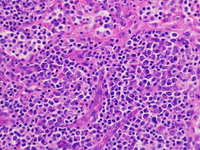

Lymph node; H&E; 20X objective.

The left supraclavicular lymph node demonstrates partial effacement of normal lymph node architecture by expansion of the interfollicular areas and dilated sinuses.  Few scattered small follicles with germinal centers are present.